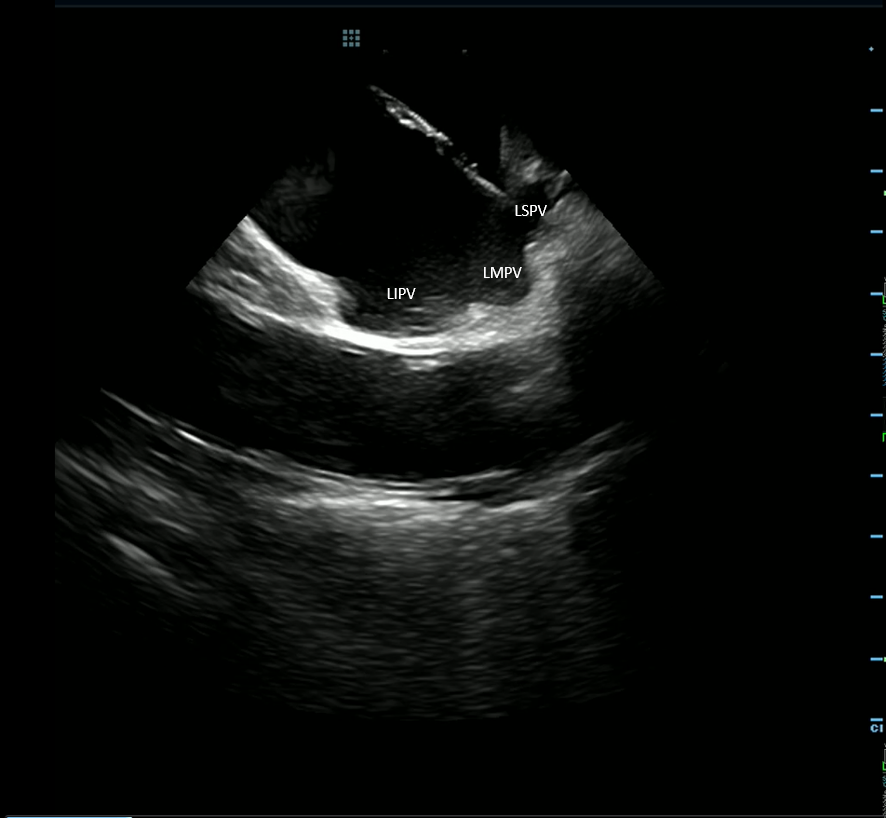

Volt released some pretty impressive 12 month data with over 80% success in paroxysmals and excellent persistent AF results. Read the simultaneous publication! kwnsfk27.r.eu-west-1.awstrack.me/L0/https:%2F%2…